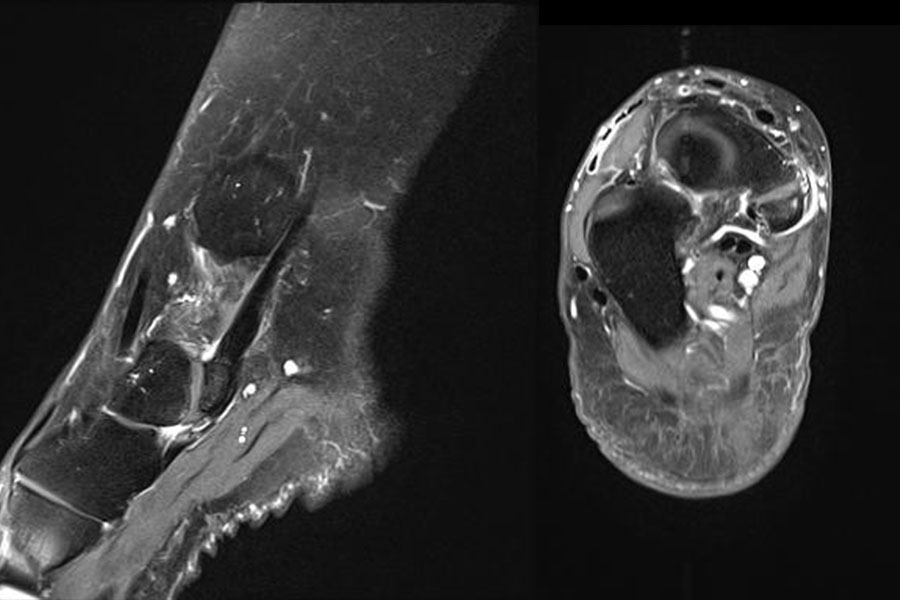

- Bei unklarem Befund kann die Bildgebung mittels MRTvervollständigt werden. Das MRT zeigt eine mögliche Aktivierung der Synchondrose bzw. erlaubt auch andere Differentialdiagnosen (Tendonose der Tibialis posterior Sehne, Verletzung Deltaband, Verletzung Pfannenband) auszuschließen (Abb. 3) 6 (Szeimies 2014).